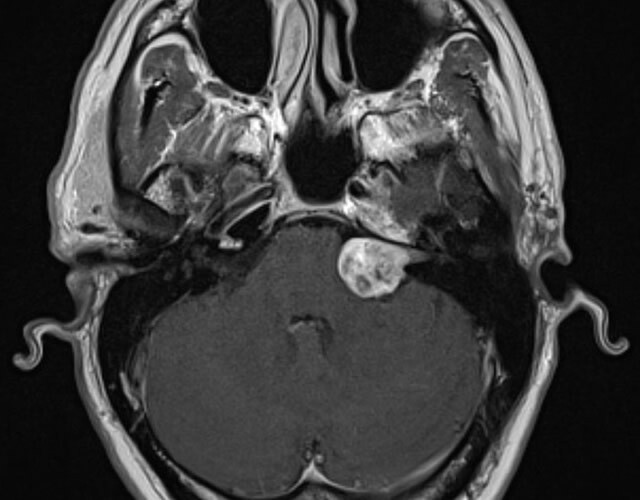

Understanding Acoustic Neuroma

Acoustic neuromas are benign brain tumours that grow on the vestibular nerve and can cause a wide range of symptoms, including: